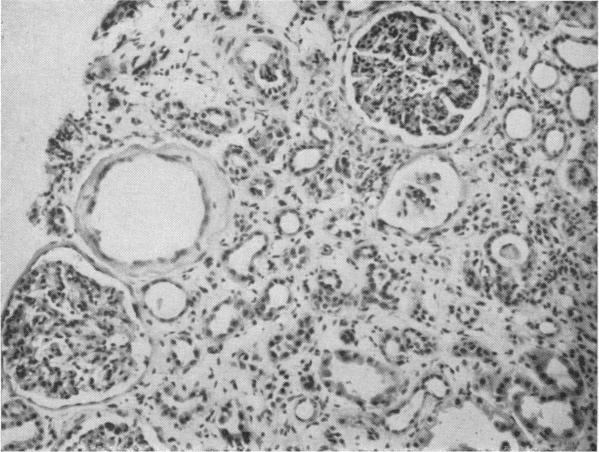

The diagnosis and treatment of renal-artery stenosis.

Br Med J. 1960 Jul 30;2(5195):327-38. doi: 10.1136/bmj.2.5195.327.